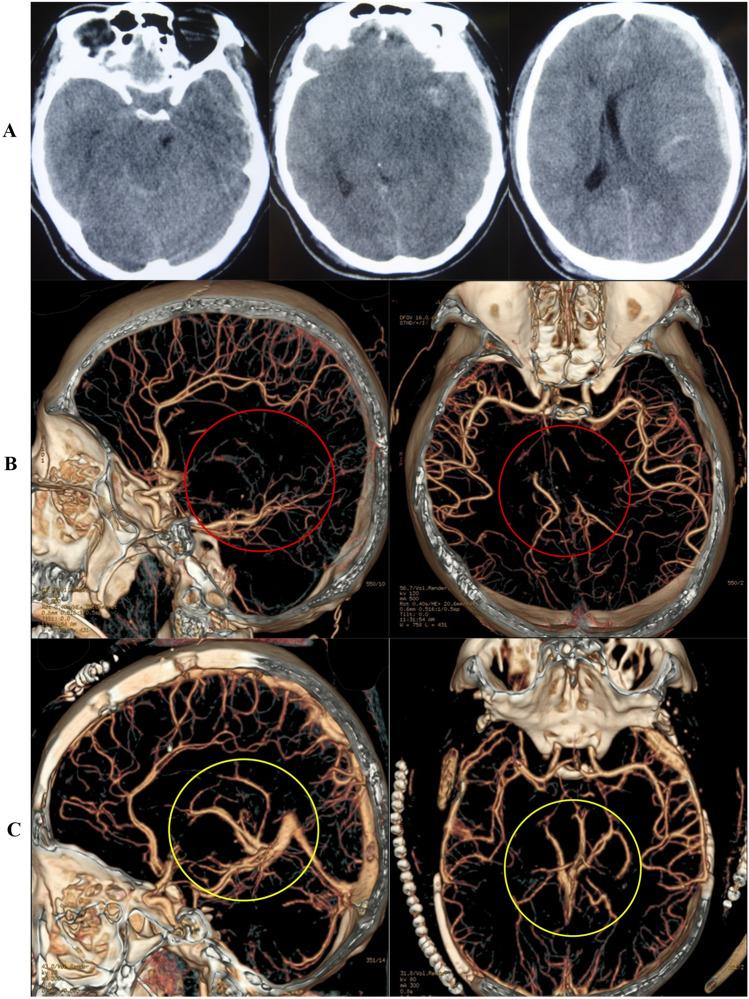

It is difficult to predict the surgical effect and outcome of severe traumatic brain injury (TBI) before surgery. This study aims to approve an evaluation method of computed tomography angiography (CTA) to predict the effect of surgery and outcome in severe TBI. Between January 2010 and January 2020, we retrospectively reviewed 358 severe TBI patients who underwent CTA at admission and reexamination. CTA data were evaluated for the presence of cerebrovascular changes, including cerebrovascular shift (CS), cerebral vasospasm (CVS), large artery occlusion (LAO), and deep venous system occlusion (DVSO). Medical records were reviewed for baseline clinical characteristics and the relationship between CTA changes and outcomes. Cerebrovascular changes were identified in 247 (69.0%) of 358 severe TBI patients; only 25 (10.12%) of them had poor outcomes, and 162 (65.6%) patients had a good recovery. Eighty-three (23.18%) patients were diagnosed with CVS, 10 (12.05%) had a good outcome, 57 (68.67%) had severe disability and 16 (19.28%) had a poor outcome. There were twenty-six (7.3%) patients who had LAO and thirty-one (8.7%) patients who had DVSO; no patients had good recovery regardless of whether they had the operation or not. Cerebrovascular injuries and changes are frequent after severe TBI and correlate closely with prognosis. CTA is an important tool in evaluating the severity, predicting the operation effect and prognosis, and guiding therapy for severe TBI. Well-designed, multicenter, randomized controlled trials are needed to evaluate the value of CTA for severe TBI in the future.